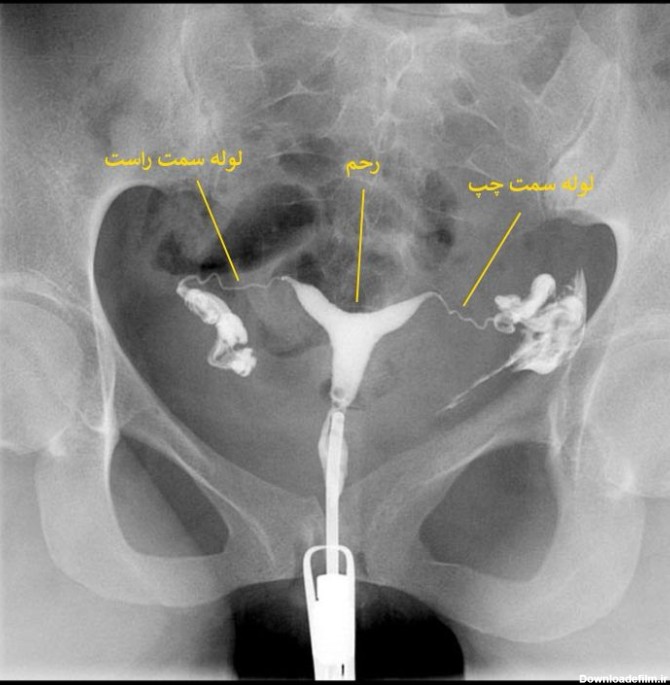

عکس رنگی رحم یا هیستروسالپینگوگرافی به معنای استفاده از اشعه ایکس برای مشاهده رحم و لولههای فالوپ است.

عکس رنگی رحم بدون درد؛ هیستروسالپنگوگرافی برای مشاهده داخل رحم و لوله های فالوپ استفاده می شود. می تواند نشان دهد که داخل رحم اندازه و شکل طبیعی دارد یا خیر.